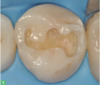

Fig 1. Rubber dam.

Figure 1